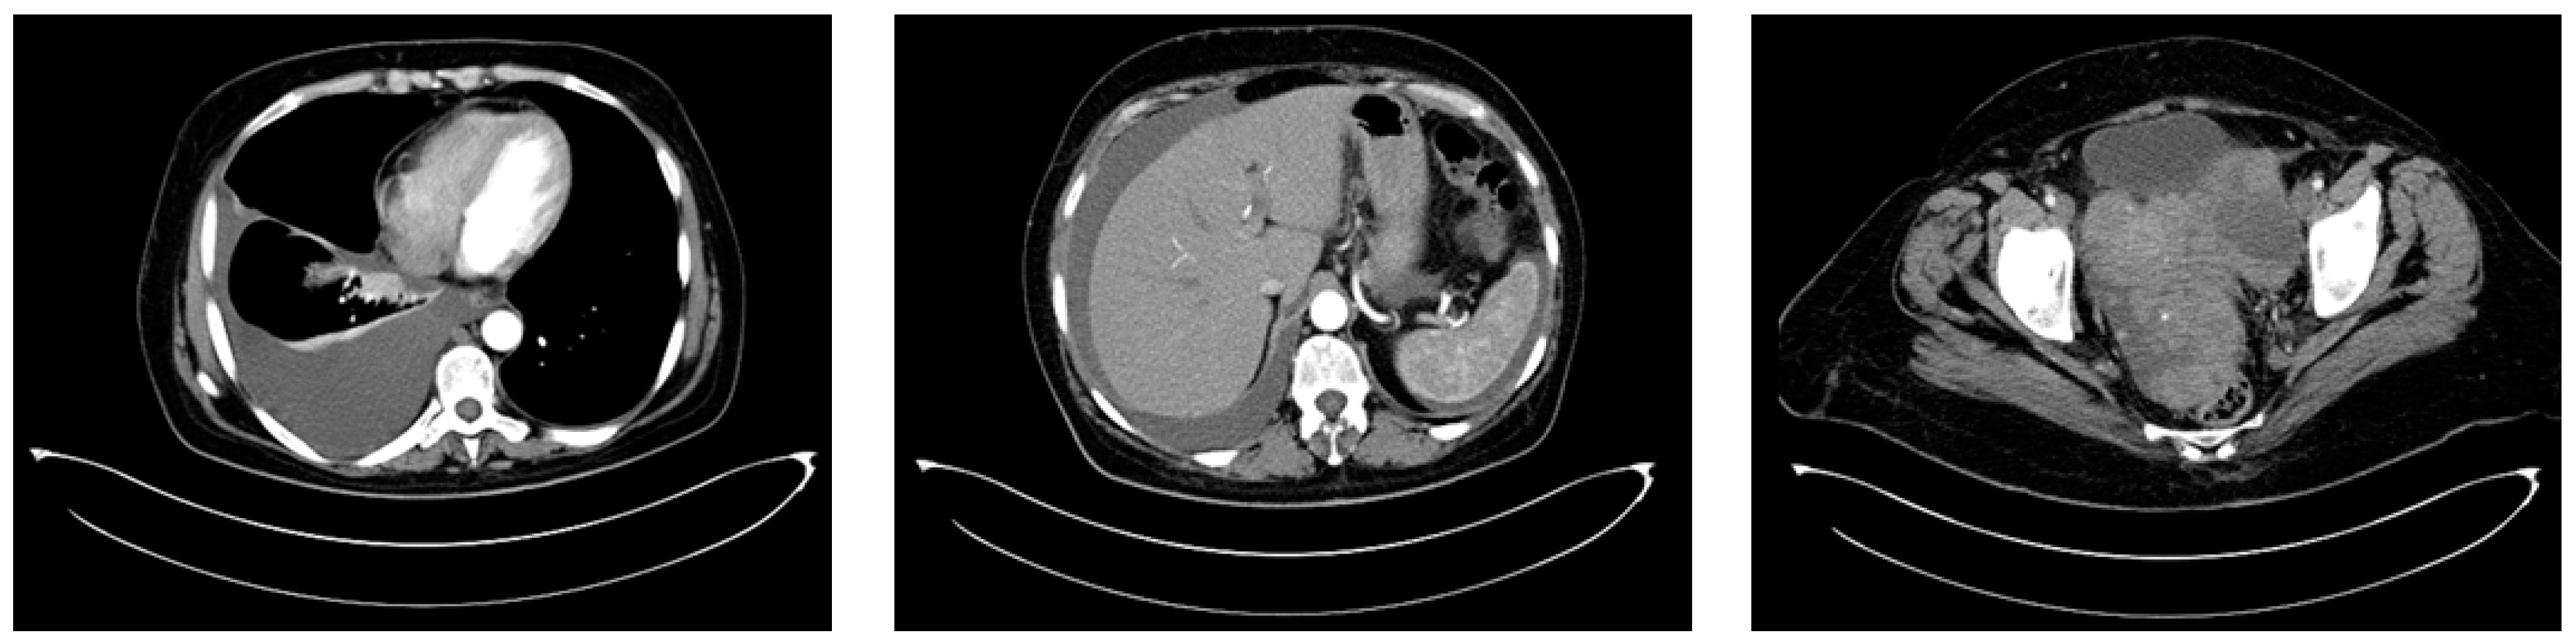

CT imaging of the thorax, abdomen, and pelvis was conducted in August 2015 and revealed a left ovarian tumor measuring 150/135/120 mm with multiple septations, cystic regions, and solid tumoral tissue, a normal-sized uterus displaced rightward and inseparable from the tumor, peritoneal carcinomatosis, a moderate amount of ascites, and a right pleural effusion occupying about one-third of the hemithorax, leading to atelectasis of the adjacent lung tissue due to compression (Figure 7).

Figure 7.

The baseline CT scan of the thorax, abdomen, and pelvis from August 2015 showing the left ovarian tumor, peritoneal carcinomatosis, ascites, and right pleural effusion, leading to atelectasis of the adjacent lung tissue.

Between September 2015 and February 2016, six cycles of Carboplatin (AUC 5) and Paclitaxel (175 mg/m2) were administered every 3 weeks, with good clinical tolerance and without hematological toxicity. A post-chemotherapy CT scan described a partial response according to RECIST 1.1. The CT imaging findings revealed a significant change in the patient’s tumoral burden, demonstrating a left adnexal tumor measuring 75/56 mm with malignant features and indistinct boundaries from the uterine fundus, suggesting direct invasion or close association. In a positive turn of events, the previously noted pleural effusion had resolved, and there was a complete disappearance of ascitic fluid, indicating a favorable response to the recent therapeutic intervention (Figure 8). After six cycles of chemotherapy, the CA-125 level was 9.04 IU/L.

Figure 8.

The first follow-up (CT scan of the thorax and pelvis, March 2016) showing partial response to treatment.